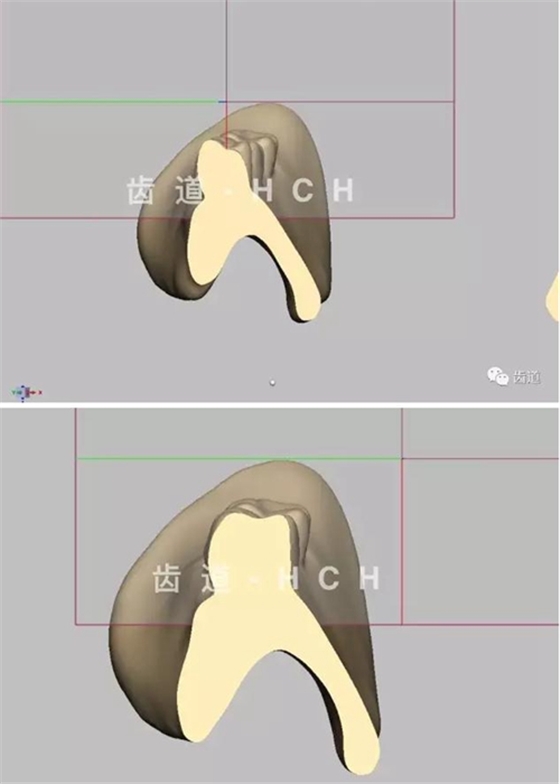

首頁義齒技術(shù) 標(biāo)準(zhǔn)全口義齒模型截圖 科貿(mào)嘉友收錄

標(biāo)準(zhǔn)全口義齒模型截圖 科貿(mào)嘉友收錄